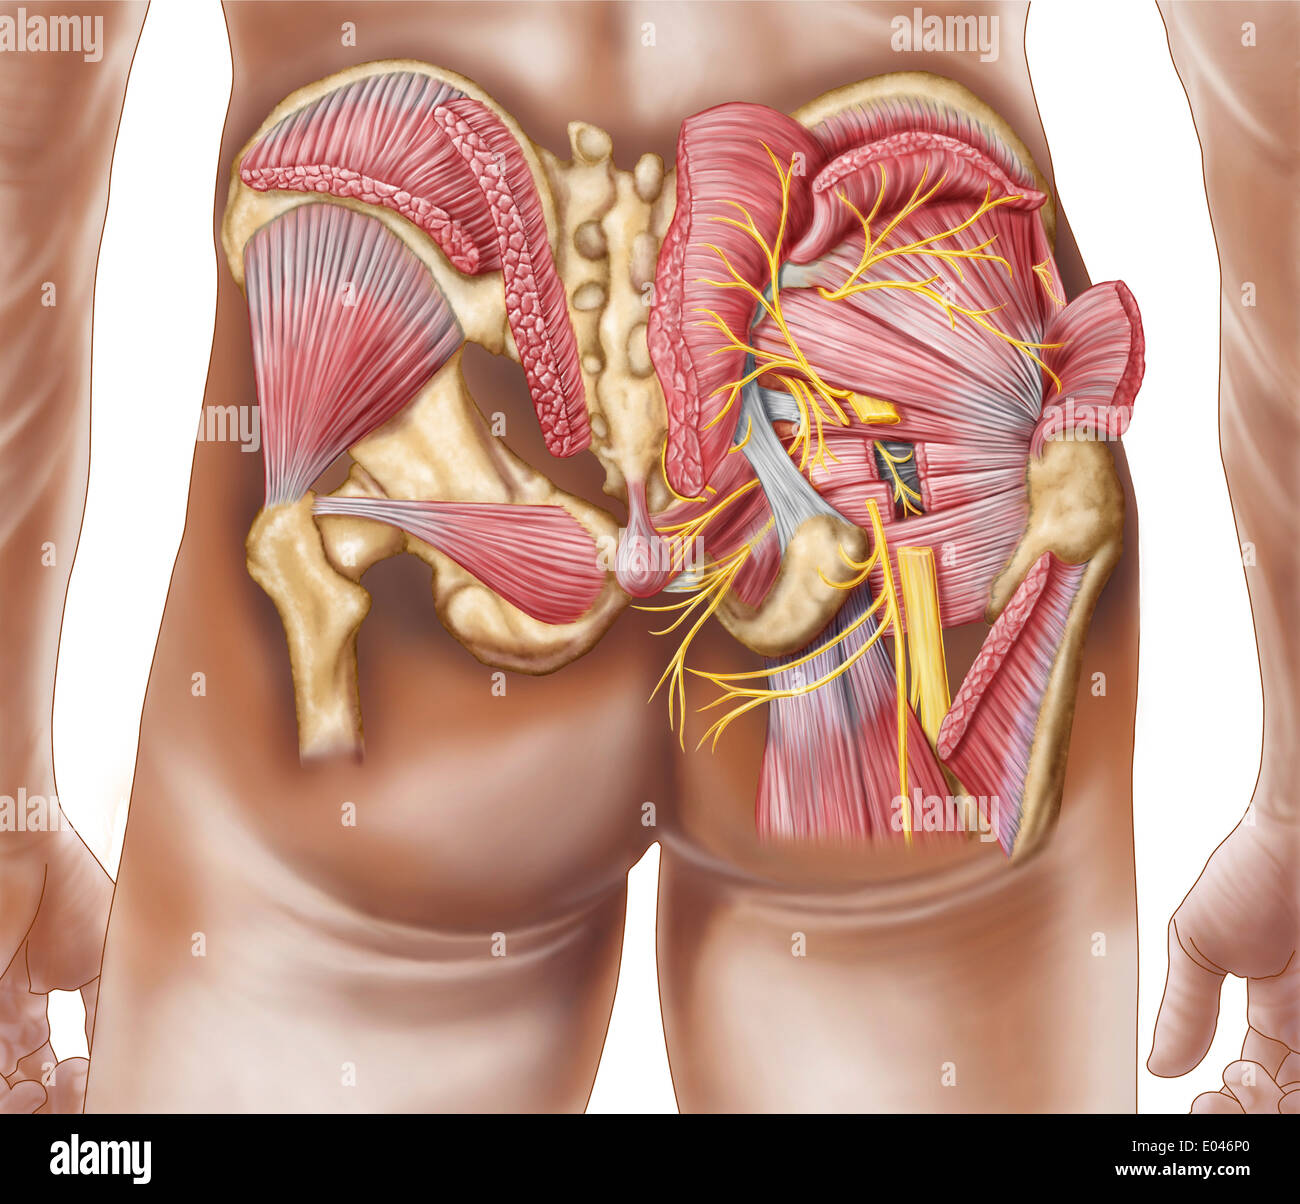

Anatomy of the gluteal muscles in the human buttocks. Stock Photohttps://www.alamy.com/image-license-details/?v=1https://www.alamy.com/anatomy-of-the-gluteal-muscles-in-the-human-buttocks-image68934600.html

Anatomy of the gluteal muscles in the human buttocks. Stock Photohttps://www.alamy.com/image-license-details/?v=1https://www.alamy.com/anatomy-of-the-gluteal-muscles-in-the-human-buttocks-image68934600.htmlRFE046P0–Anatomy of the gluteal muscles in the human buttocks.